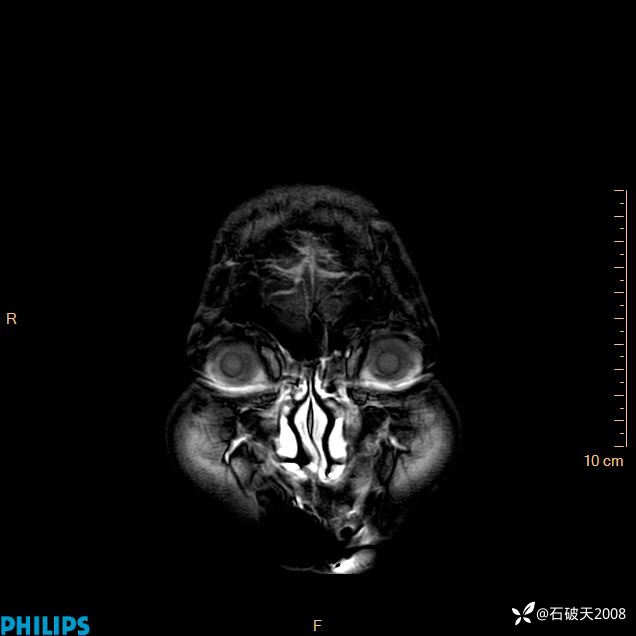

2024.2.21MR

增强冠状位